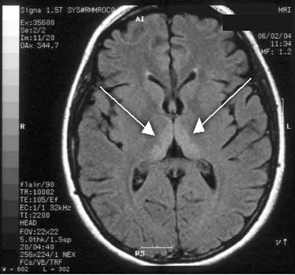

Haematological and biochemical test results were largely normal, but her serum levels of creatinine (0.04 mmol/L; normal range [NR], 0.05–0.10 mmol/L) and urea (2.2 mmol/L; NR, 2.5–6.1 mmol/L) were slightly low, and her INR (international normalised ratio) was 2.0 (NR, 0.8–1.2). There were also some elevated levels in her liver function test results: γ-glutamyl transferase, 60 U/L (NR, < 50 U/L); alanine aminotransferase, 486 U/L (NR, < 55 U/L); and bilirubin, 32 U/L (NR, 0–19 U/L). Cerebrospinal fluid (CSF) examination and magnetic resonance imaging (MRI) were also undertaken to exclude intracranial causes. The CSF findings were normal, but the MRI revealed bilateral thalamic lesions (Figure 2).

Given the new clinical features and her MRI result, a diagnosis of Wernicke’s encephalopathy was made. Thiamine deficiency was suspected to be secondary to hyperemesis gravidarum. Interestingly, her serum thiamine level was only marginally low at 64 nmol/L (normal range, 66–200 nmol/L). Therapy with pyridoxine, folic acid and intravenous thiamine replacement was commenced.

She made a rapid clinical recovery. Visual acuity returned to normal within 3 days and her ataxia, gaze limitation and neuropathy improved. Repeat MRI imaging 7 days later showed moderate resolution of the hyperintensities. Our patient went on to successfully deliver a healthy baby girl at 37 weeks’ gestation.

Our case is unusual in that visual deterioration was the first symptom of an evolving thiamine deficiency. There was a delayed presentation of the classical triad of Wernicke’s encephalopathy — ataxia, mental confusion and ocular gaze problems. Moreover, in our case, MRI scanning was able to detect sensitive neurological changes, raising the suspicion of thiamine deficiency. This information was important in prompt treatment of the condition when clinical signs began to emerge. Indeed there are reports of the usefulness of MRI imaging in diagnosing cases of Wernicke’s encephalopathy.7